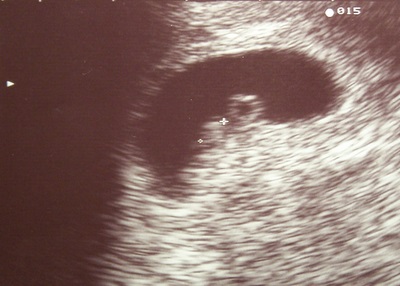

És akkor rólunk: ma voltam Tóth dokinál UH-n, és láttam, ahogy pulzált, aminek pulzálnia kell!!!

Kaptunk képecskét is, mindjárt felteszem.

gyengébbek kedvéért: a két kis + között van az embrió, 4,2 mm-es, a másik a szikhólyag...